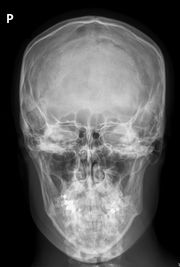

Lékařské využití

Poté, co Röntgen objevil využití pro pozorování kostních struktur, se rozvinulo jeho užívání v lékařském snímkování. Rentgenové záření může být využito pro zobrazení detailů kostí a zubů (skiagrafie), popřípadě za pomoci vhodných technik i ke zkoumání měkké tkáně (denzitografie, subtrakční skiagrafie, tomografie). Radiologie je specializovaný obor lékařství využívající rentgenového záření v diagnostice. Toto je pravděpodobně nejčastější využití rentgenového záření.